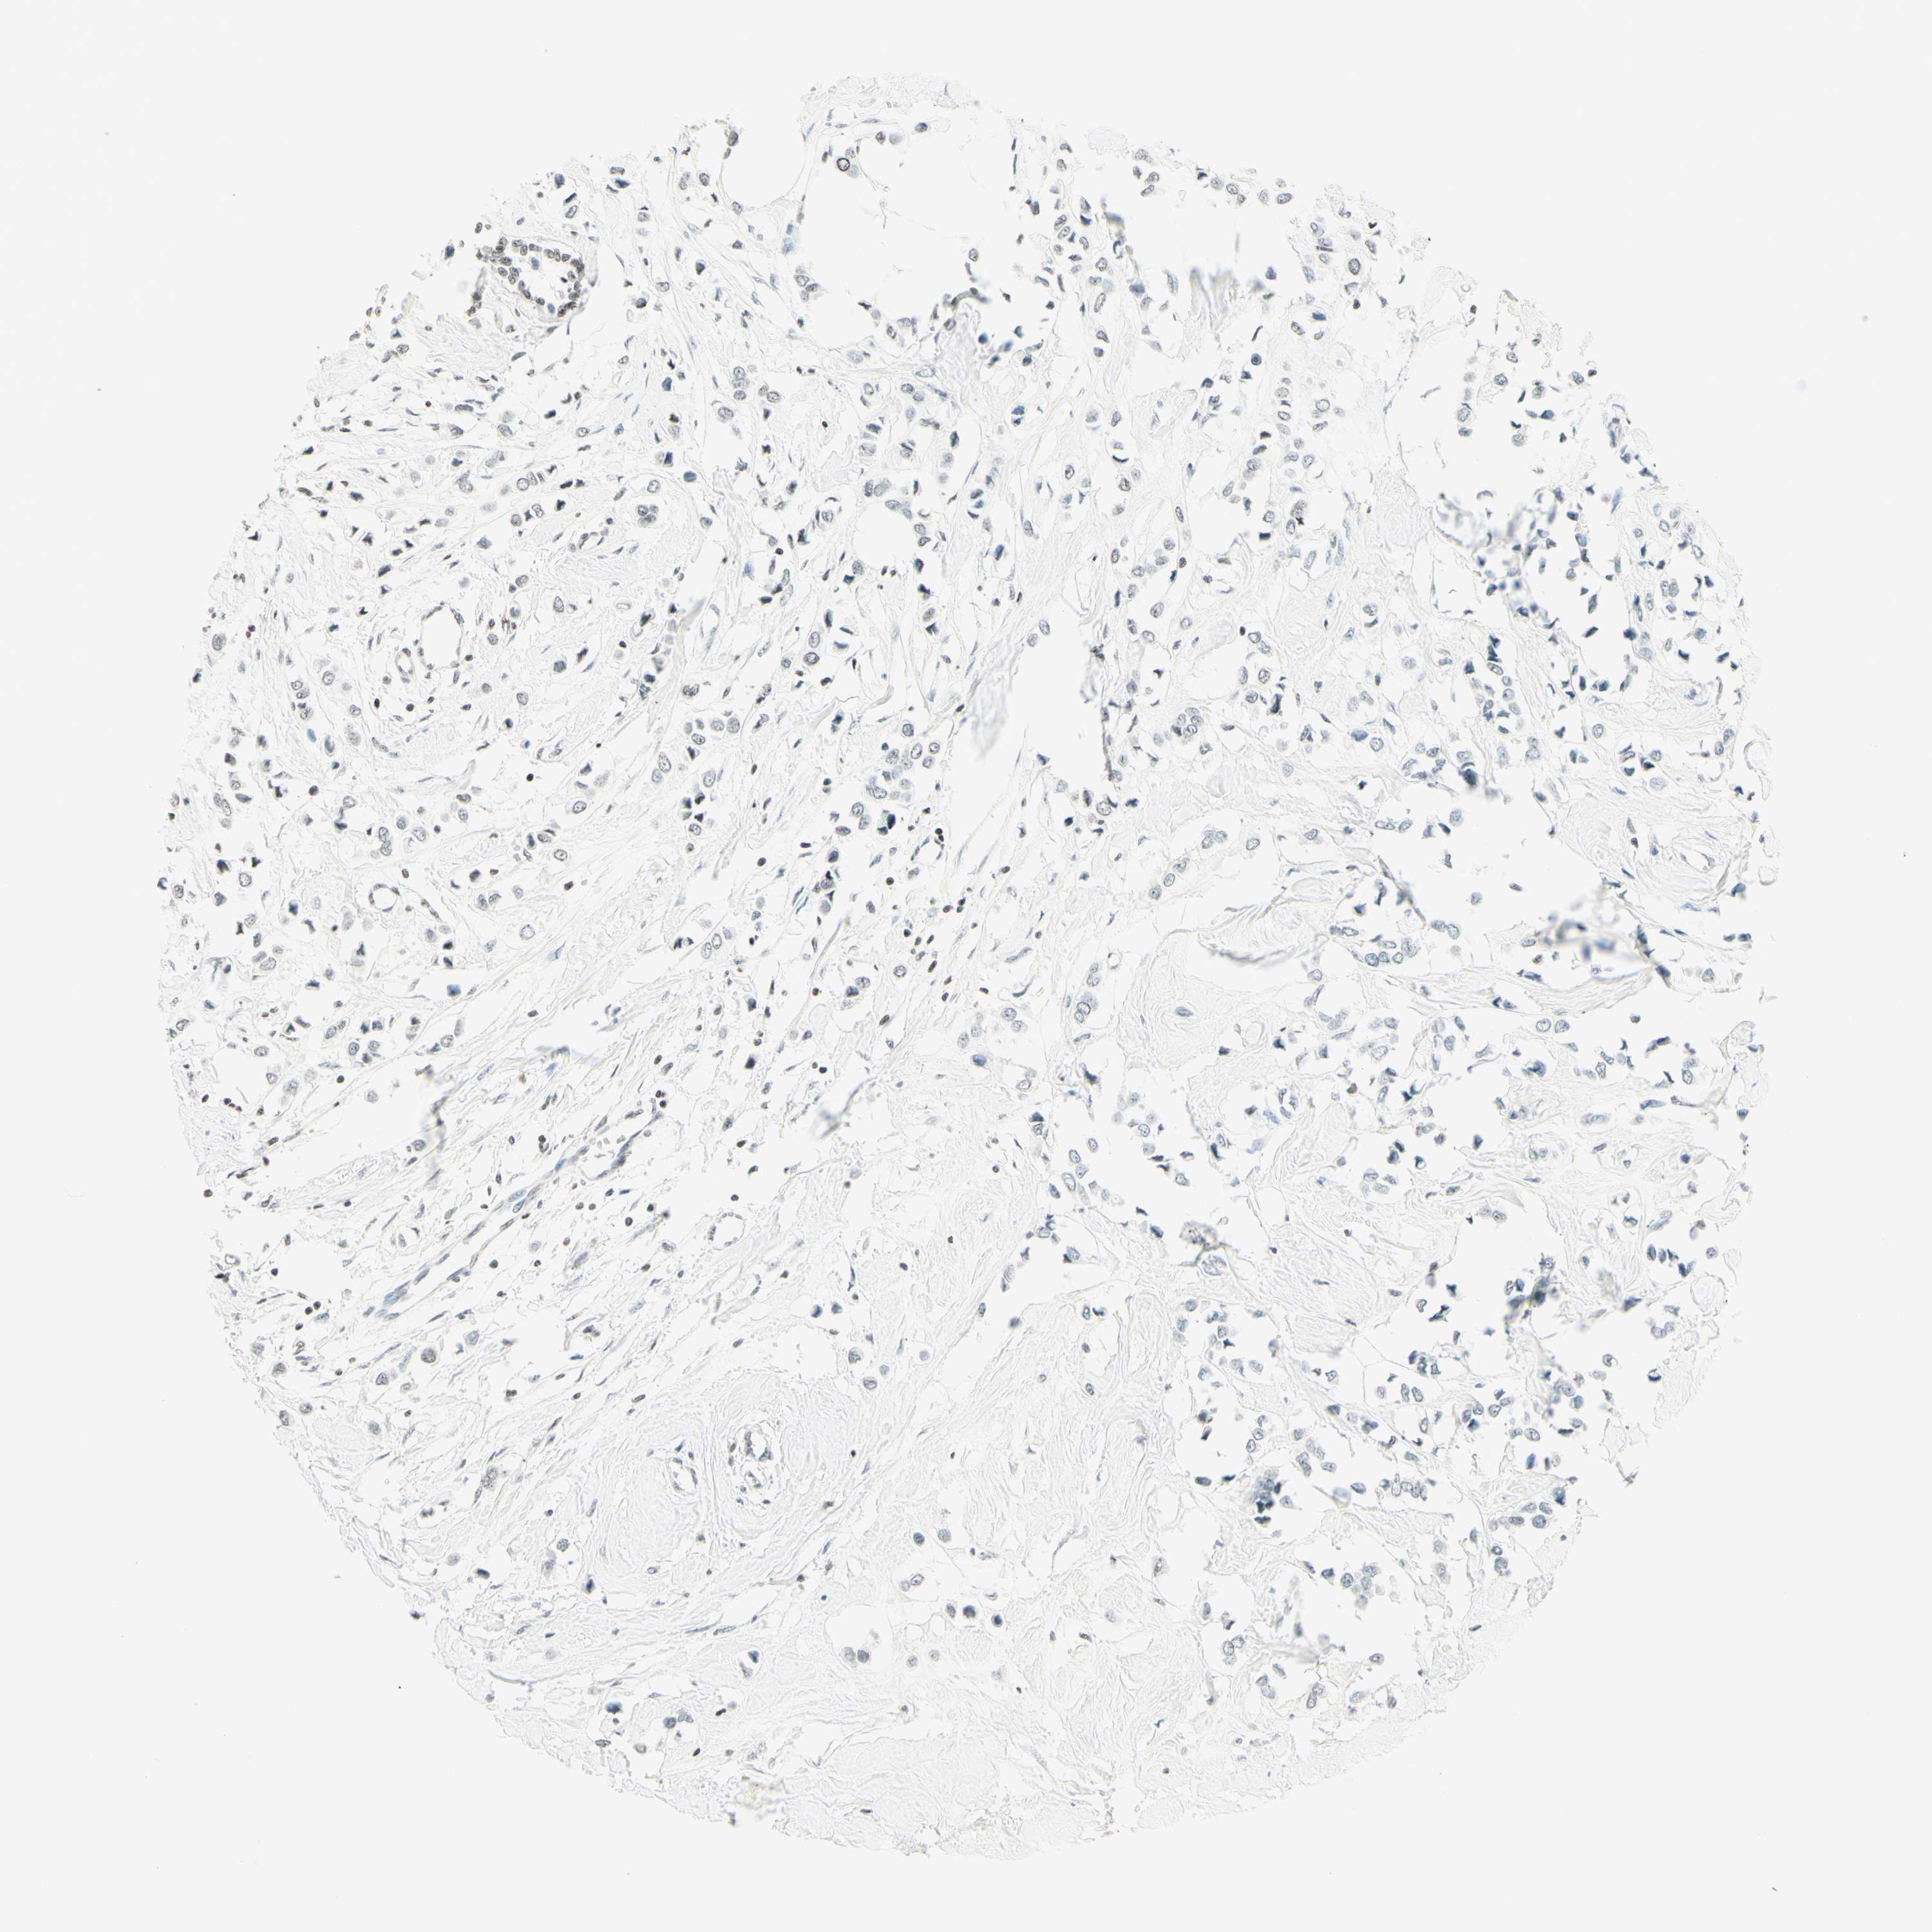

BRCA TCGA BRCA VALIDATION PROTEIN EXPRESSION

ANTIBODIES

AND

VALIDATION